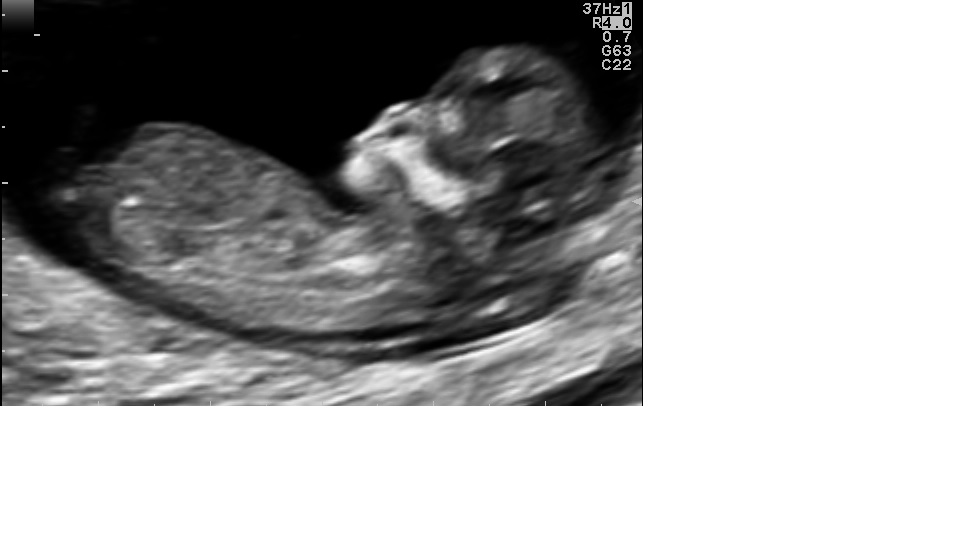

So Curious...what do you think...boy or girl ;-)